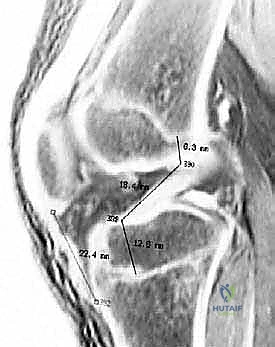

شكل 2: صورة رنين مغناطيسي سهمي عبر الجانب الجانبي للركبة، تُظهر نمط الكدمة العظمية المميزة لإصابة الرباط الصليبي الأمامي الحادة (سهم رفيع). هذه الكدمات تعكس الصدمة التي تحدث عندما يندفع عظم الساق إلى الأمام على عظم الفخذ.

2. الرنين المغناطيسي (MRI): هو المعيار الذهبي. لا يُظهر فقط القطع في الرباط، بل يكشف عن الإصابات المصاحبة في الغضاريف الهلالية والأربطة الأخرى.

شكل 1: صورة رنين مغناطيسي سهمي تُظهر نمط الكدمة العظمية المميزة لإصابة الرباط الصليبي الأمامي الحادة (سهم رفيع). لاحظ زيادة الإشارة على الجانب الخلفي من الهضبة الظنبوبية الجانبية والجانب البعيد من عظم الفخذ عند الثلمة النهائية.